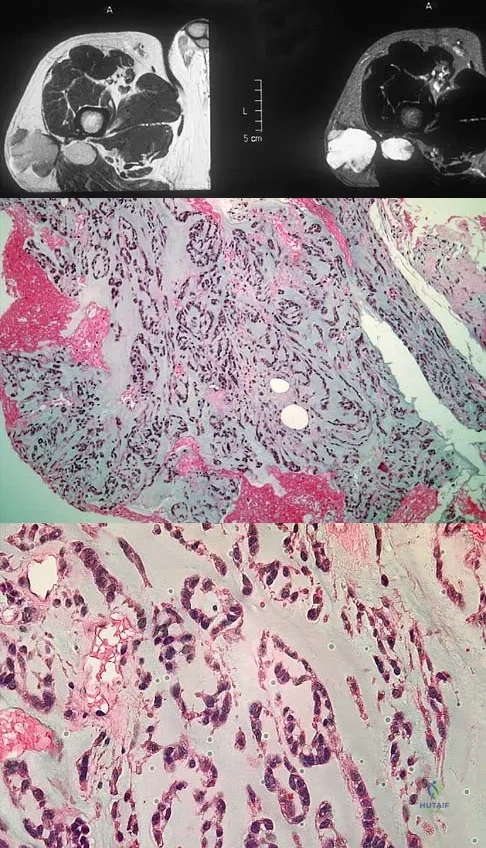

A 40-year-old man has a painless mass around his left ankle. He notes minimal growth over the past year. An MRI scan is shown in Figure 73a, and biopsy specimens are shown in Figures 73b and 73c. What is the most likely diagnosis?

Explanation:

The biopsy specimen is a low-power view of a soft-tissue sarcoma with a biphasic pattern of epithelial cells and fibrous spindle cells that are typical of a synovial sarcoma. A deep, painless soft-tissue mass greater than 5 cm in size is suspicious for a sarcoma. The imaging in this patient is indeterminate and the patient requires a biopsy for an accurate diagnosis. The biopsy reveals a tumor with a biphasic appearance consistent with a synovial sarcoma. These tumors are slow growing, occur primarily in the lower extremities, and are found in a younger demographic population compared to malignant fibrous histiocytoma and liposarcoma. They can occur in a biphasic pattern with clumps of epithelial cells and fibrous spindle cells or in a monophasic pattern. Synovial sarcomas stain positively for keratin. Keratin is positive in nearly all biphasic types and in many tumors of the monophasic fibrous type. Sixty percent of these tumors are found in the lower extremity. The area around the knee is the most common location, followed by the ankle and foot. Epithelioid and clear cell sarcomas are found associated with tendon sheaths of the hand and feet and are generally smaller in size. Epithelioid sarcoma may resemble granulomatous inflammation histologically; clear cell sarcoma is composed of nests of clear cells with occasional multinucleated giant cells. Pigmented villonodular synovitis is found within the synovium and is characterized by a villous histologic appearance with hemosiderin-laden macrophages. Malignant fibrous histiocytoma has a storiform histologic pattern with an abundance of pleomorphic cells. Enzinger FM, Weiss SW: Soft Tissue Tumors, ed 3. St Louis, MO, Mosby, 1995, p 757.